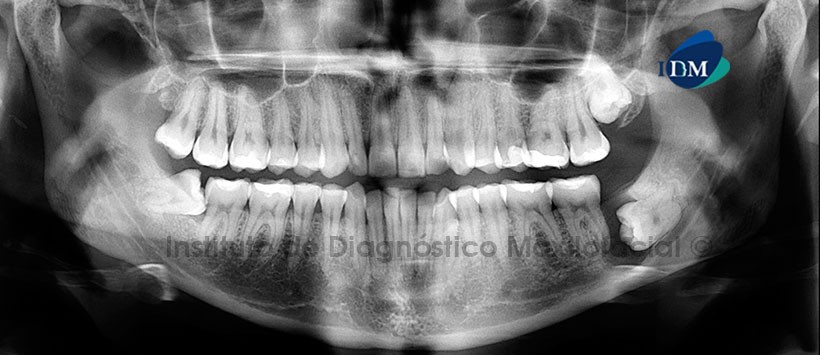

Paciente de sexo femenino de 32 años de edad acude al Instituto de Diagnóstico Maxilofacial para evaluación general de ambos maxilares.

A la evaluación panorámica se aprecia neumatización alveolar de ambos senos maxilares, apiñamiento dentario del sector anterior, múltiples restauraciones, pieza 28 retenida en posición vertical y la pieza 48 impactada en posición horizontal en relación a la cara distal de la pieza 47. Sin embargo lo más resaltante es una imagen radiolucida ubicada en cuerpo mandibular izquierdo (localizada en distal de la pieza 37) de forma redondeada y limites definidos la cual está asociada a la pieza 38 (Figura 1).